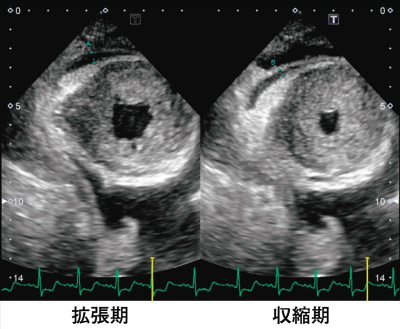

検査所見:尿所見:蛋白3+、糖(-)、沈渣に異常を認めない。血液所見:赤血球 417 万、Hb 13.0 g/dL、Ht 41 %、白血球 6,800、血小板 28 万。血液生化学所見:総蛋白 9.8 g/dL、アルブミン 2.8 g/dL、総ビリルビン 0.7 mg/dL、AST 34 U/L、ALT 26 U/L、LD 345 U/L(基準 176〜353)、ALP 225 U/L(基準 115〜359)、 尿素窒素 18 mg/dL、クレアチニン 2.3 mg/dL、血糖 79 mg/dL、HbA1c 5.3% (基準 4.6〜6.2)、Na 138 mEq/L、K 4.9 mEq/L、Cl 106 mEq/L、Ca 10.8 mg/dL、P 2.1 mg/dL、脳性ナトリウム利尿ペプチド<BNP> 253 pg/mL(基準 18.4 以下)。 CRP 0.1 mg/dL。心電図は心拍数 91/分の洞調律で肢誘導の低電位、左房負荷および不完全左脚ブロックを認める。胸部エックス線写真で心胸郭比は 52 % で、両側に少量の胸水を認める。心エコー図を別に示す。

この患者の心エコーで認められる所見はどれか。

e. 左室壁の著明な肥厚